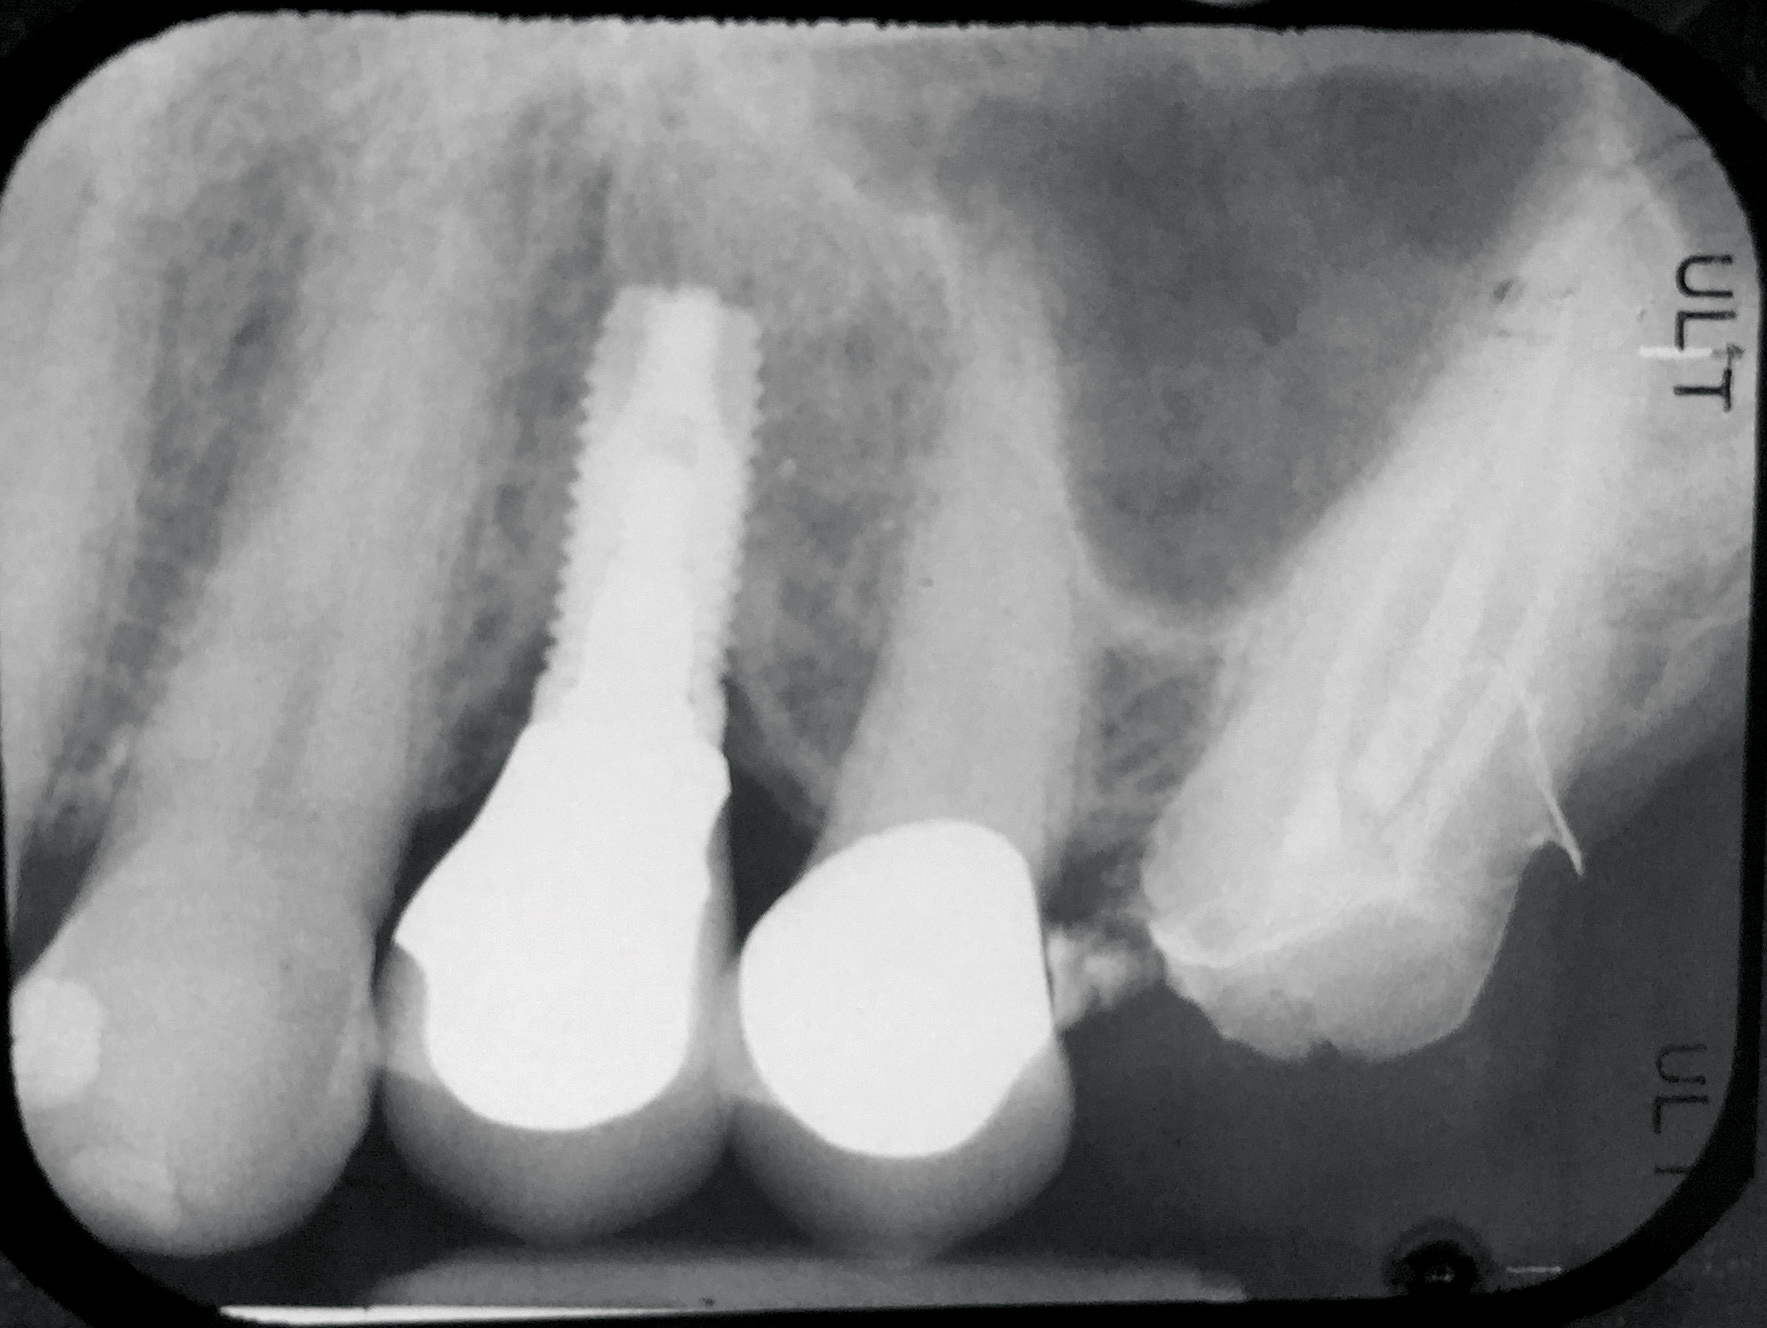

Fig 13. Radiograph depicting peri-implantitis.

Figure 13

Excess Cement Leading to Peri-implantitis

If all implant-supported crowns could be designed for screw retention, no discussion of excess cement would be necessary. However, screw retention is not always possible depending on the location of the access opening and because of the unesthetic appearance in anterior restorations or the mesial/distal angulation of the implant compromising the path of insertion (Figure 12). Residual cement left after crown cementation on implants can lead to peri-implant inflammation, peri-implantitis, and eventual loss of the implant (Figure 13 through Figure 15).25 The presence of lingering excess cement can encourage the development of bacterial colonization and peri-implantitis. Conversely, when too little cement is used, voids in the cement layer can occur and the prosthesis can become loose.26 The deeper the implant crown margin, the more difficult it is to remove excess cement.27